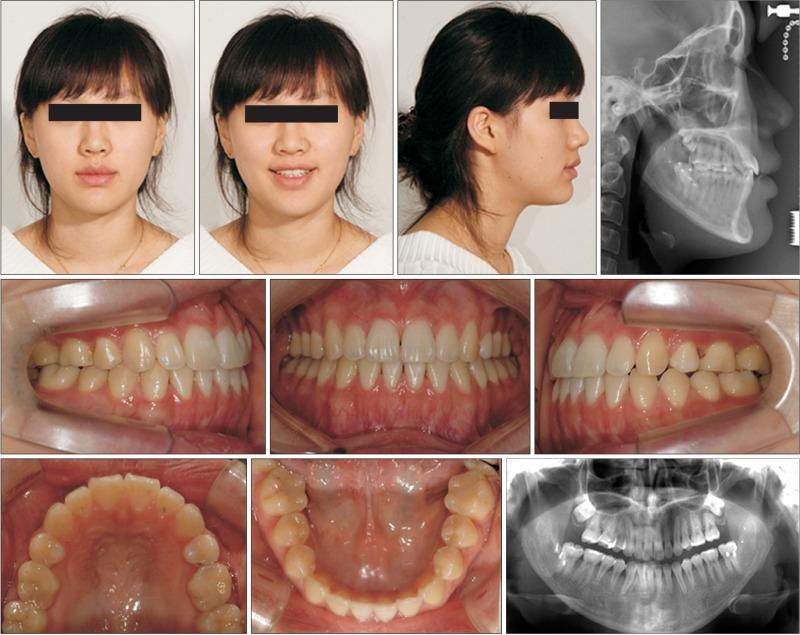

Because of the potential morbidity and complications associated with surgical procedures, limiting the extent of orthognathic surgery is a desire for many orthodontic patients. An eighteen-year-old woman had a severe Class III malocclusion and required bi-maxillary surgery. By changing the patient's maxillary occlusal plane using orthodontic mini-implants, she was able to avoid the maxillary surgery; requiring only a mandibular setback surgery. To accurately predict the post-surgery outcome, we applied a new soft tissue prediction method. We were able to follow and report the long-term result of her combined orthodontic and orthognathic treatment. The changes to her occlusal plane continue to appear stable over 6 years later.

由于外科手术存在潜在的发病率和并发症,许多正畸患者都希望限制正颌手术的范围。一名18岁女性患有严重的III类错牙合畸形,需要进行双颌手术。通过使用正畸微型种植体改变患者的上颌咬合平面,她得以避免上颌手术,仅需进行下颌后缩手术。为了准确预测术后结果,我们应用了一种新的软组织预测方法。我们能够跟踪并报告她正畸与正颌联合治疗的长期结果。6年多后,她咬合平面的变化仍保持稳定。